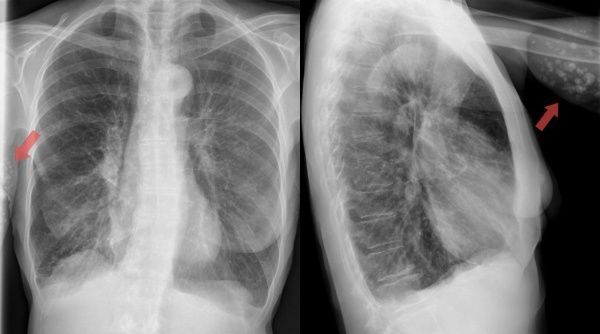

В целом ситуация на данный момент такова. 1025 человек лечатся в инфекционных стационарах республики, пневмония диагностирована у 1017 из них. Коронавирус лабораторно подтвержден у 271 пациента. В тяжелом состоянии остаются 178 человек, 18 подключены к аппаратам ИВЛ, еще 396 нуждаются в кислородной поддержке.